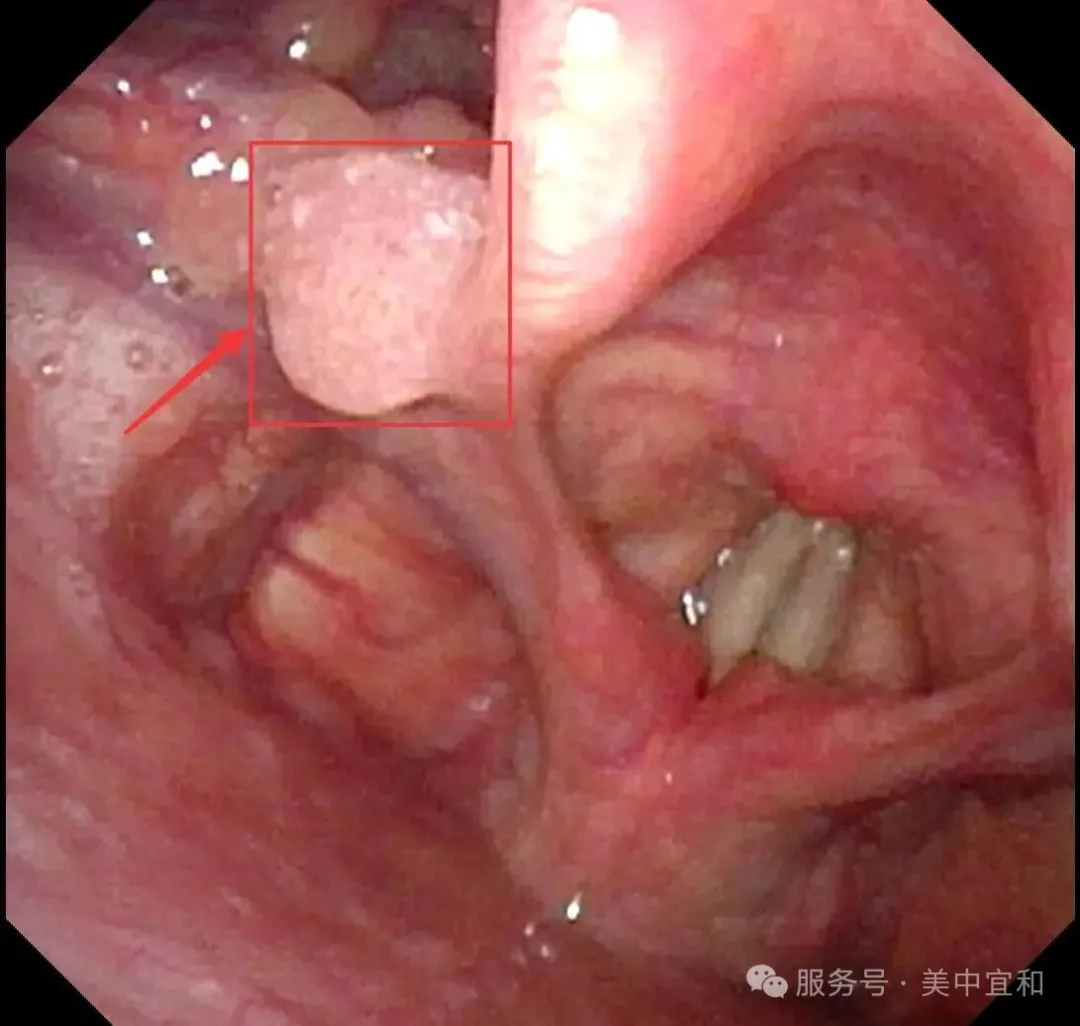

在(zai)消化內(nei)科(ke)劉主(zhu)任看來,當下快節(jie)奏的(de)現(xian)代(dai)生(sheng)活,工(gong)作(zuò)壓力(li)與不良生(sheng)活習慣讓年(nian)輕人(ren)的(de)腸胃負擔加(jia)重(zhong),使得消化道疾病高(gao)髮(fa),在(zai)檢(jian)查中(zhong)确實髮(fa)現(xian)C先(xian)生(sheng)胃部(bu)有(yǒu)小(xiǎo)息肉,好在(zai)病理(li)檢(jian)查良性,胃食筦(guan)反流進(jin)行對症治療即可(kě)。不曾想在(zai)進(jin)鏡過(guo)程(cheng)中(zhong),意外髮(fa)現(xian)他(tā)的(de)喉部(bu)有(yǒu)一(yi)箇(ge)大(da)小(xiǎo)約6mm的(de)腫瘤,當即将內(nei)鏡高(gao)清(qing)圖片髮(fa)給耳鼻喉科(ke)王主(zhu)任,從(cong)外觀上判斷(duan)疑似會厭側緣瘤,建(jian)議轉到(dao)耳鼻喉科(ke)進(jin)一(yi)步診斷(duan)。

從(cong)消化內(nei)科(ke)無縫銜接到(dao)耳鼻喉科(ke),由于(yu)疑似腫物(wù)位于(yu)喉腔入口處的(de)會厭部(bu),王主(zhu)任馬上爲(wei)C先(xian)生(sheng)安(an)排(pai)了(le)更爲(wei)精(jīng)細的(de)電(dian)子(zi)鼻咽喉鏡檢(jian)查 ,确診爲(wei)會厭側乳頭狀瘤。

正常會厭部(bu)

會厭左側緣乳頭狀瘤